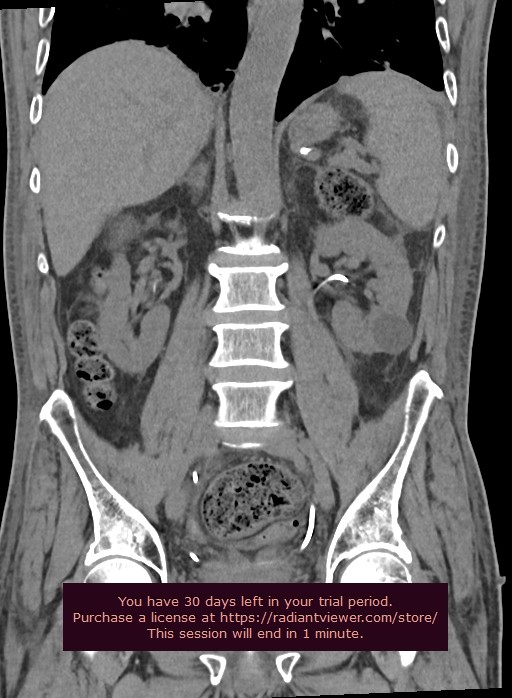

The patient was stable and exhibited signs of recovery following the surgical placement of JJ stents in the kidneys. After 4 days the improvement was evident in the non-contrast control MDCT scans with visualization on double JJ stent in both ureters conducted after the surgical procedure. Moreover, there were no indications of any free fluid in the surrounding kidney tissue.

Figure 6. Control MDCT shows no trace of any free fluid in the surrounding kidney tissue after the surgical placement of the JJ stents.